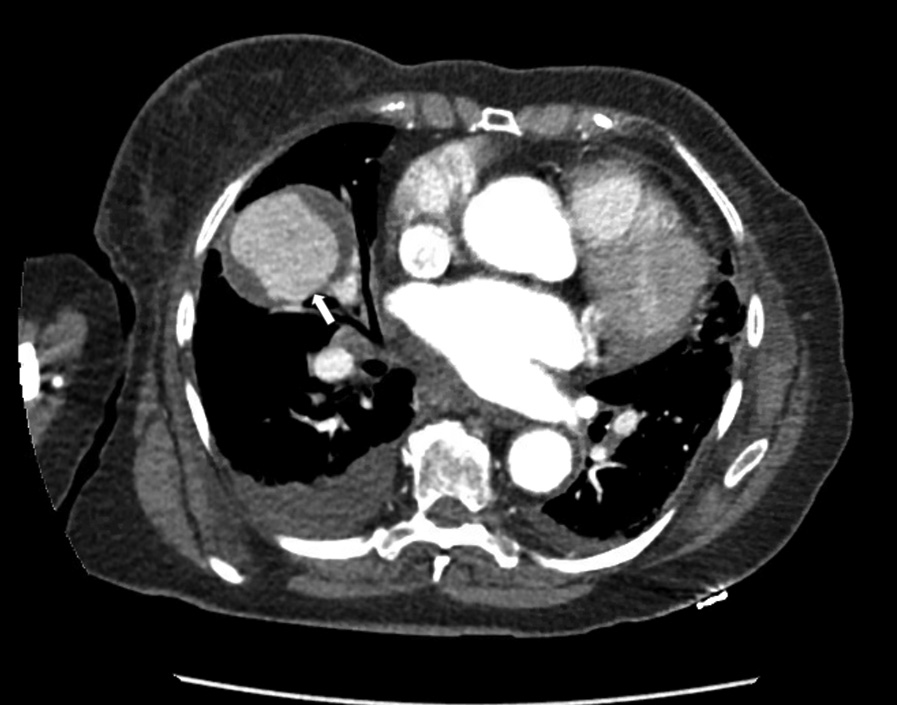

患者胸部CT扫描如下(图2A)。出院后行正电子发射计算机断层扫描成像(PET)扫描,发现右中叶肿块间歇性增大,摄取值小(标准化摄取值为3.7)(图2B)。经临床评估后,行增强CT,再次显示右侧中叶肿块,肿块明显强化(图3)。

图3 增强CT扫描显示右中叶肿块。右肺病变(箭头)可见造影剂提示假性动脉瘤活动性出血。